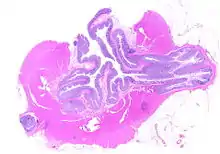

Pathophysiology

The precise mechanisms by which diverticula are formed are unknown.[1] Multiple theories have been proposed including genetic susceptibility, diet, intestinal motility, changes in the microbiome, and inflammation. One leading theory suggests that diverticula form in weakened areas of the colon wall that are subjected to increased pressure.[1] The strength of the colon wall is known to decrease with age.[1] Previous theories proposed that impacted fecal matter and certain foods would get stuck in diverticula (thereby causing trauma), which caused poor blood flow, death of the affected intestinal wall cells, and intestinal perforation.[1] Newer theories have called this paradigm into question.[1]